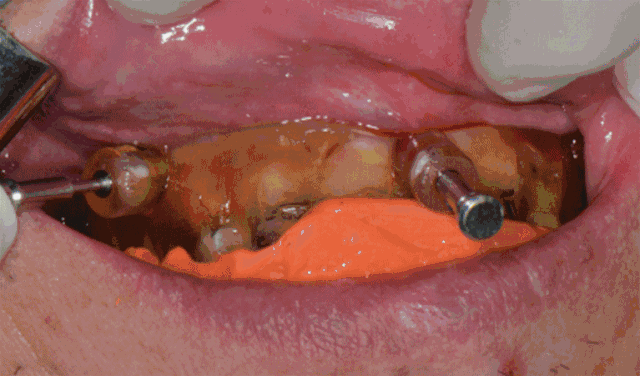

精彩案例:

靖佳齿科赠送价值1000元种植模型套装/人(现场实操口扫扫描数据,即刻切削完成种植上部修复)